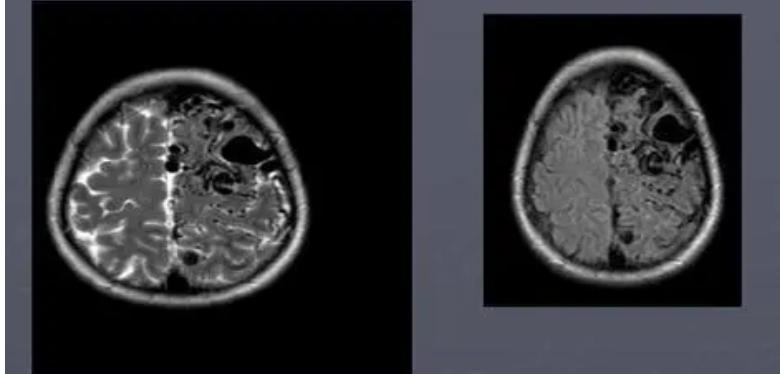

流空效应(flowing void effect):心血管内的血液由于流动迅速,使发射MR信号的氢原子核离开接受范围,所以测不到MR信号,在T1加权像或T2加权像中均呈黑影,即流空效应,这一效应使心腔和血管显影。

应用SE技术,以一定速度流动的液体产生流空效应,呈无或低信号。产生此效应的原因在于:射频脉冲所激发的质子在接收线圈获取MR信号时,因流动已移出成像层面,而此时成像层面内原部位的质子为流入的非激发质子,故不能产生MRI信号。

与流动液体相比,周围静止组织如:血管壁发出的MRI信号不变。血液在血管中流动是产生此效应的典型示例,较快速流动的血液呈无或低信号,与静止呈中等信号的血管壁形成鲜明对比,清楚显示出血管的形态结构。这是SE技术的MRI的一个显著优点,也是MRI显示心脏大血管解剖结构的基础。

如果血流速度较慢,SE技术MRI图像上血管内可有少量信号呈灰色,而慢速血流则产生强白信号。分析MRI图像时应注意此效应所致的血管内信号变化。